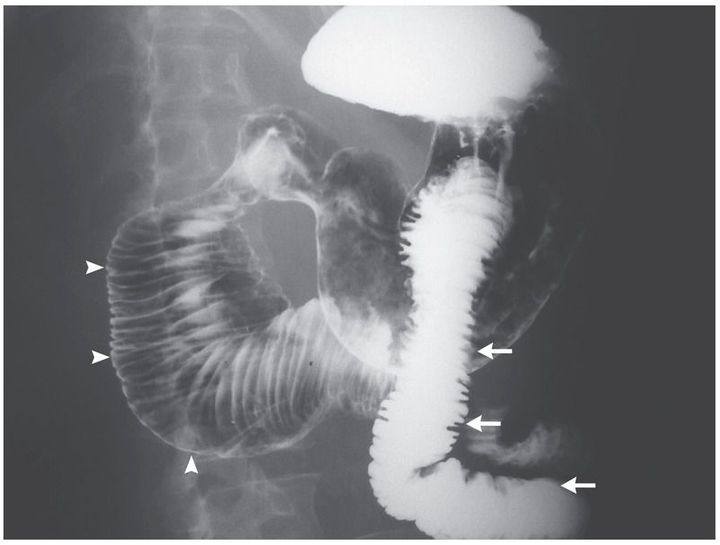

A 46-year-old woman who had a 7-year history of systemic sclerosis and used methotrexate for its treatment presented to the emergency department with abdominal pain, persistent nausea, and vomiting of undigested food that had begun 3 months earlier. On physical examination, she was noted to have skin with woody induration and loss of normal elasticity, dry eyes, and a decreased oral aperture. The physical examination of the abdomen was normal. Upper gastrointestinal endoscopy showed no evidence of mechanical obstruction or esophageal damage; a barium-swallow examination revealed duodenal distention of up to 8 cm in diameter (arrowheads), without evidence of mechanical obstruction, and normal intestinal caliber of the jejunum (arrows). Megaduodenum secondary to systemic sclerosis was diagnosed after assessments for other conditions, including amyloidosis, Chagas’ disease, and Whipple’s disease, were unrevealing. Assessments included biopsy of the distal duodenum and testing for antibodies to Trypanosoma cruzi and Tropheryma whipplei. Placement of a jejunostomy tube for feeding resulted in a reduction in the patient’s symptoms and a weight gain of nearly 4 kg over a period of 8 months. Gastrointestinal manifestations of systemic sclerosis may include esophageal and gastric dysmotility; duodenal involvement is rare.